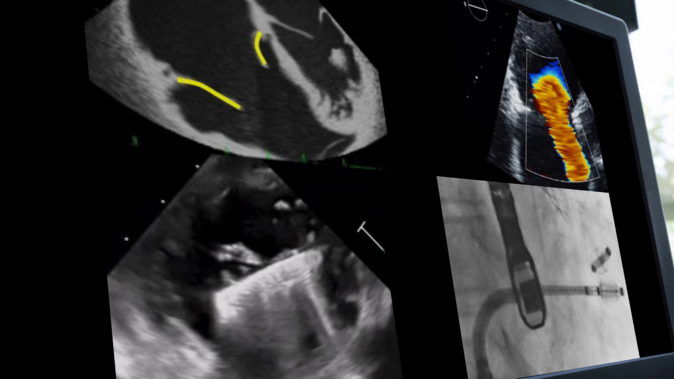

Optimal use of cardiac imaging to plan and guide transcatheter LAA closure

Optimize left atrial appendage (LAA) closure outcomes through expert use of cardiac imaging. This session details the role of various imaging modalities in pre-procedural planning, intraprocedural guidance, and post-procedural assessment. Gain practical insights on transesophageal echocardiography, computed tomography, intracardiac echocardiography, and their integration to enhance procedural...

From innovation to integration: the evolution of 4D intracardiac echocardiography in structural heart interventions

Learn how 4D intracardiac echocardiography (ICE) is reshaping structural heart procedures. This EuroPCR 2025 session takes you through the latest in imaging technology—highlighting the benefits of 4D ICE and AI integration in improving the safety, precision, and efficiency of mitral and tricuspid interventions. From valve repair...